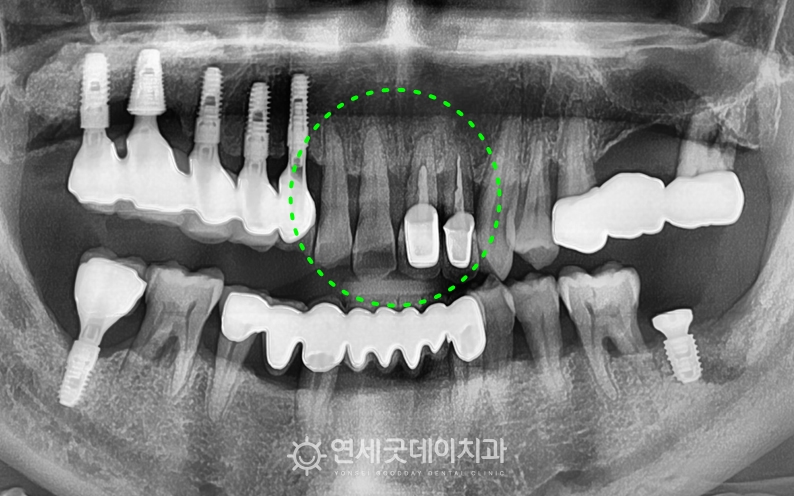

▲ 타원에서 진행한 앞니크라운 부위, 치료 전 X-ray

타원에서 신경치료 후 크라운을 씌웠던 부위에

구내 모습에서도 전체적으로 치은의 부종이 심하고

환자분은 전치부를 발치한 뒤 i-GBR 급속골이식을 통해

▲ 치료 중 – 앞니 임플란트 식립

급속골이식은 치유능력이 가장 좋은 시기인

약 2개월 후 앞니 잇몸뼈가 잘 아물었으며,